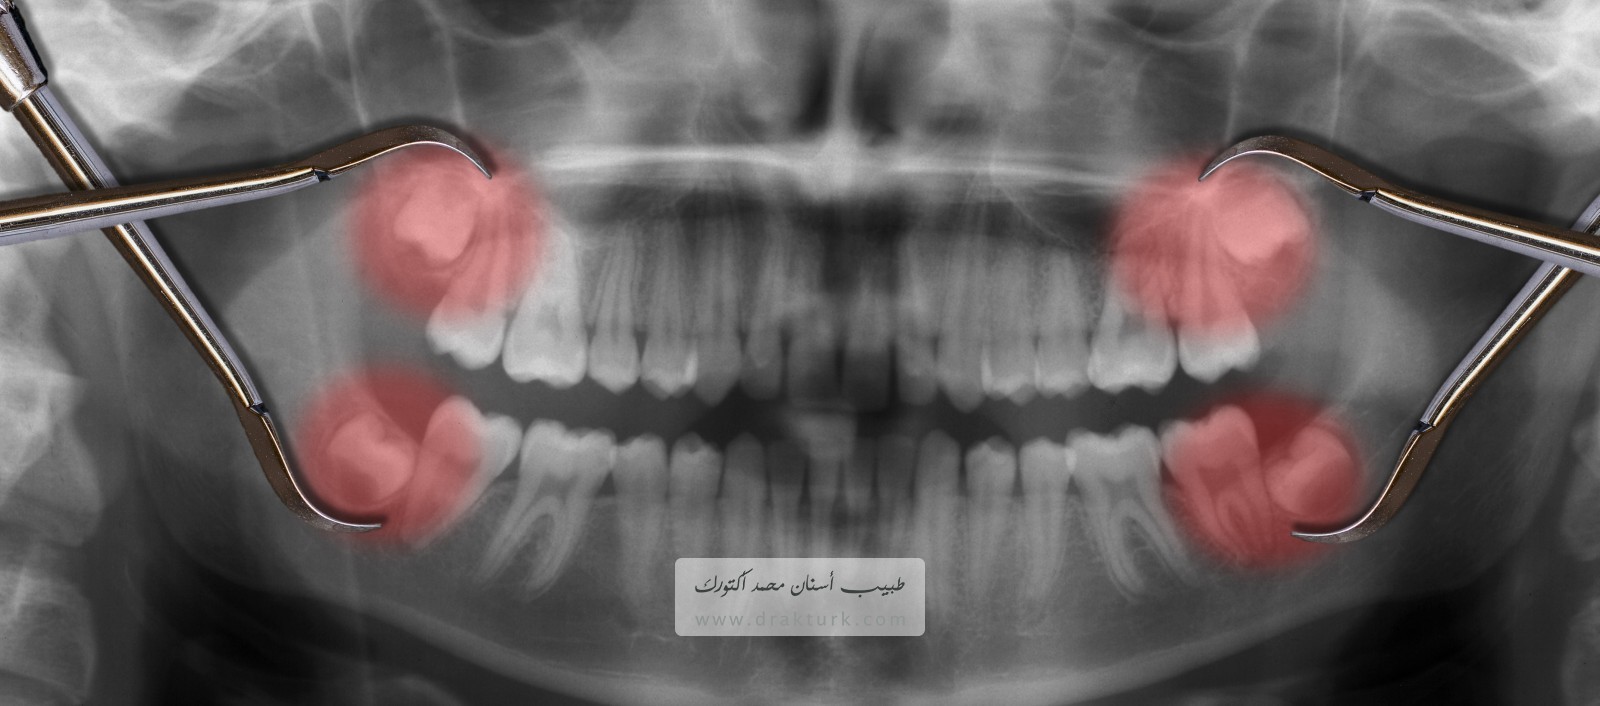

قلع ضرس العقل هو إجراء جراحي لإزالة ضرس عقل أو أكثر؛ ويقصد بذلك الضروس الأربعة الدائمة التي تنبت لدى البالغين الموجودة في الأركان الخلفية من الفم بأعلاه وبأسفله.

إذا لم يكن لدى أحد ضروس العقل مساحة للنمو (ضرس عقل مطمور) وأدى ذلك إلى ألم أو عدوى أو غيرها من المشاكل بالأسنان، يُرجح أنك ستقتلعه. يجوز إجراء جراحة قلع ضرس العقل عن طريق طبيب أسنان أو جراح فم.